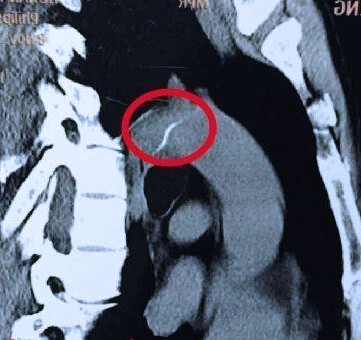

感觉在喉结以下喉镜又看不到的鱼刺就有点麻烦了,可能卡在食道某一个位置,这就需要食道镜或者胃镜进行检查了,也可以行CT,毕竟医生也是肉眼凡胎,透视不了,胃镜的话可以一路看到胃,顺便可以看看你的胃功能如何。食道里的鱼刺不是很好取,需要评估位置风险,如上所说,卡在危险的地方,可能有钱也保不了命。但是,只要不是在危险的地方,医生还是会比较顺利的取出来的。

还有就是喉镜、胃镜一路检查下来也没发现鱼刺,但自己感觉总是有的这种情况,这样的话可能就要行具体部位的CT扫描了,可能是鱼刺扎进肉里面去了,喉镜胃镜这些检查根本发现不了,如果是这种鱼刺比上述就更麻烦一点了,同样需要评估位置和风险,可能需要行手术切开取出。